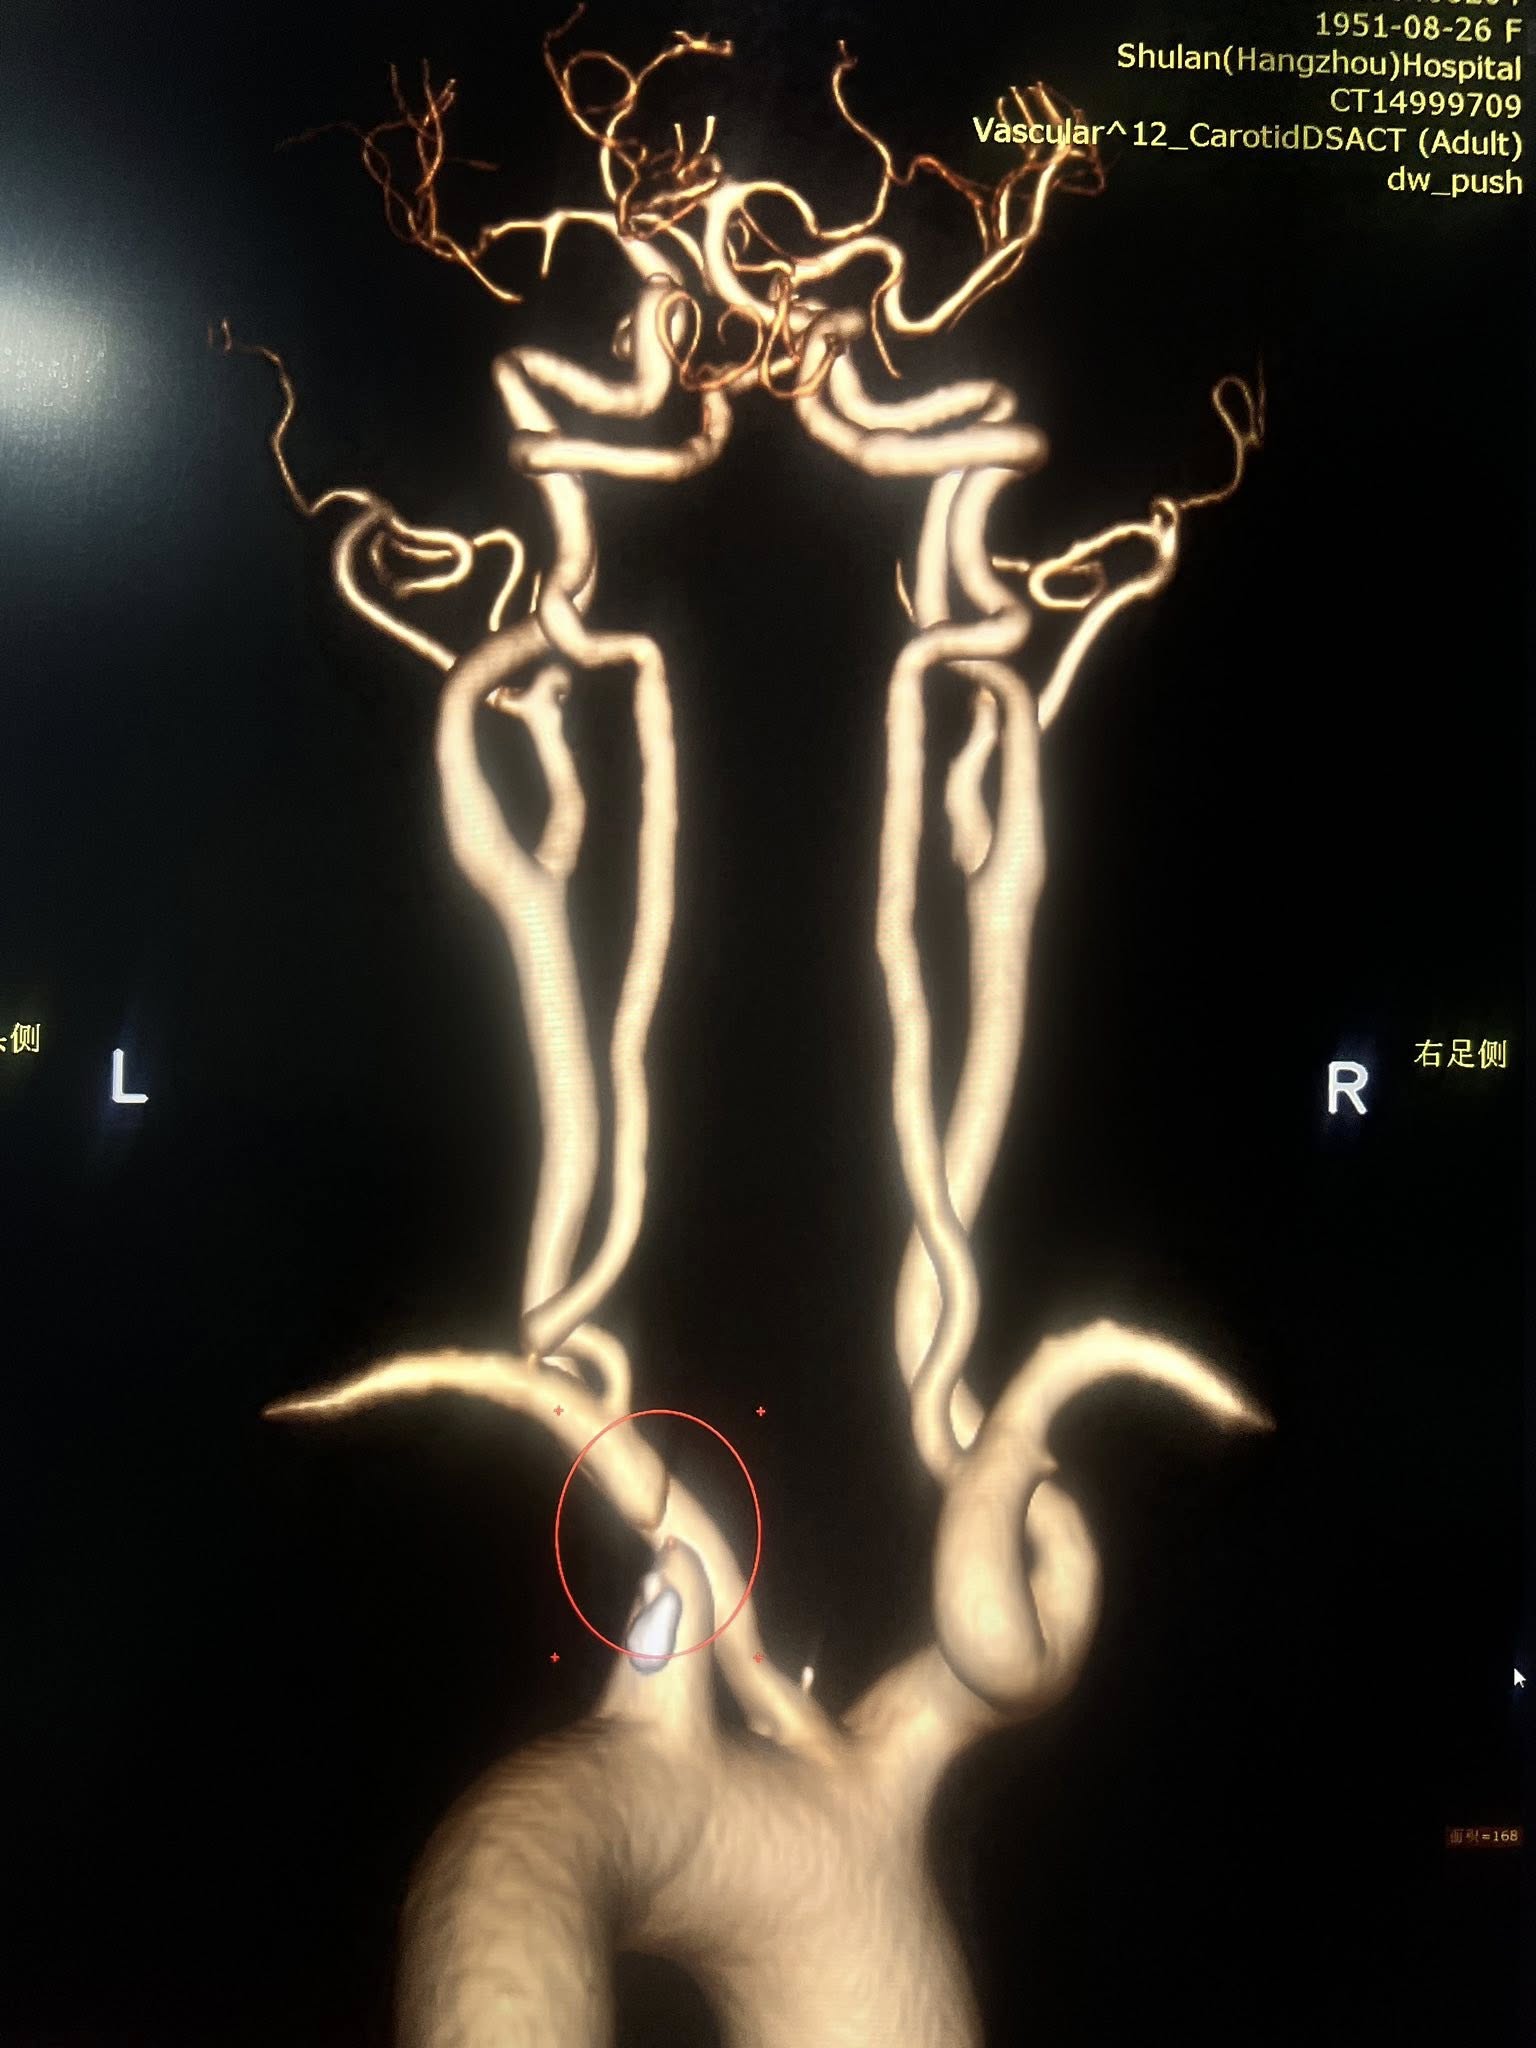

• تصوير الشرايين (CTA أو MRA أو DSA): لتحديد مكان وشدة الانسداد